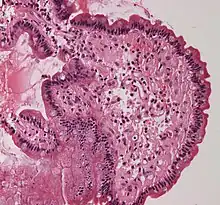

Amyloidosis, dystrophic calcification Small bowel duodenum with amyloid deposition 20X

Small bowel duodenum with amyloid deposition 20X Amyloidosis, Node, Congo Red